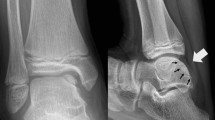

Distinct differences in the histology, OCT, and microscopy images (Fig. 2) were observed between samples from different ICRS groups as well as average NIR spectra (Fig. 3c), thus highlighting the sensitivity of these optical techniques. Data from the 700–1100 nm spectral region correlated (p < 0.0002) with collagen orientation, collagen content, and PG content (Table 1, Fig. 3). The average NRMSEs indicated that combination of only spectral smoothing with 1–8 neurons was the most reliable approach (11.7%), when compared to SNV (11.8%) and MSC (11.9%) normalization, and 1st derivative (12.2%) and 2nd derivative (12.5%) preprocessing. Furthermore, both the adaptation of IVS (10.4%) and the condition-specific models combined with IVS (9.2%) systematically decreased the average NRMSE. The average thickness values of the superficial and deep zones were 77 ± 42 µm and 698 ± 215 µm, respectively.

Representative examples of ICRS0, ICRS1 and ICRS2 grades visualized using light microscopy (a, Safranin-O stained) and OCT (b), along with the cartilage surface and cartilage-subchondral bone interface (c) automatically segmented from the OCT image. Followed by PLM (d,e) images with depth-wise collagen orientation angle (solid line) and birefringence (Bir., dashed line) profiles, DD (f,g) images with depth-wise OD profile, and FTIR-based (h,i) depth-wise profiles of collagen and PG contents. The interface between the superficial and deep zones is presented with the black triangle.